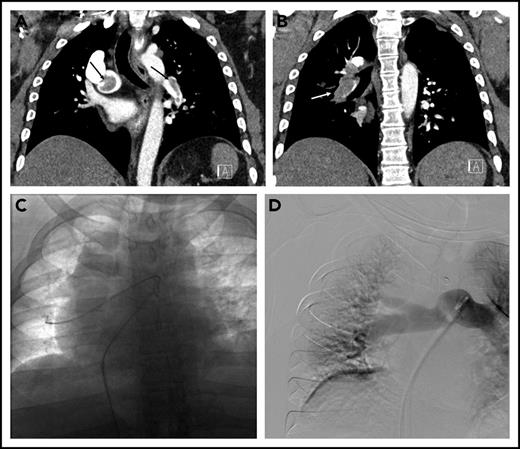

The patient was started on a therapeutic dose of UFH, and diagnostic testing for PE was initiated. Laboratory data included troponin-I of 0.35 ng/mL (normal < 0.04 ng/mL), an N-terminal-pro-brain natriuretic peptide level of 3590 pg/mL (normal < 300 pg/mL), and lactate 2.4 mmol/L (normal < 1.6 mmol/L). Chest computed tomography (CT) angiogram showed a saddle PE in the main pulmonary artery as well as obstructive lobar and segmental thrombus (Figure 1A-B). The RV to left ventricular (LV) ratio was 1.3 (normal < 0.9). Transthoracic echocardiography showed a severely dilated and hypokinetic right ventricle and an estimated pulmonary artery systolic pressure of 61 mmHg.

Submassive pulmonary embolism in patient 2. (A) Coronal CT demonstrating thrombus (arrows) in the right main and left lower-lobe pulmonary arteries. (B) Bulky thrombus is identified in the right lower-lobe pulmonary artery (arrow). (C) Wires and catheters traversing the thrombus in the right main and lower-lobe pulmonary artery. (D) Completion pulmonary angiography demonstrating good pulmonary perfusion.

The hospital’s Pulmonary Embolism Response Team (PERT), consisting of faculty from cardiothoracic surgery, pulmonary/critical care medicine, and interventional radiology (IR), was activated. After a discussion of treatment options, the PERT’s consensus was to proceed with CDT. In the IR suite, the pulmonary arterial system was catheterized (Figure 1C). The mean plasminogen activator (PA) pressure was 37 mmHg. Bilateral multisidehole infusion catheters were positioned within the thrombus. Recombinant tissue PA (rt-PA) was administered through each catheter at a rate of 0.67 mg/h (total dose 1.3 mg/h). UFH was infused through one of the sheaths to maintain a PTT less than 2 times the institutional norm during the infusion. After 18 hours (24 mg rt-PA total), the patient was brought back to the IR suite, where repeat measurements showed a mean PA pressure of 20 mmHg. Repeat angiography showed that the main right and left pulmonary arteries and lobar branches were largely thrombus free (Figure 1D). The sheaths and catheters were removed, and therapeutic-level UFH was resumed. An echocardiogram the next day showed improved RV function. He was discharged on warfarin 4 days postoperative. One month after discharge he reported feeling well without residual dyspnea or other symptoms.